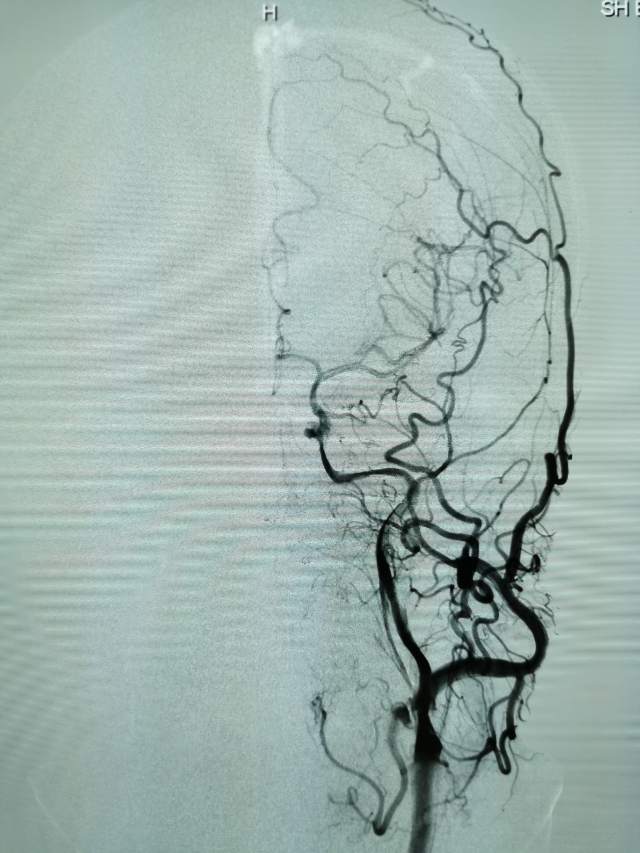

儿子很是着急,多方打听后,转来我院。入院后的评估发现左侧颈内动脉已经闭塞2个月了,左侧的大脑半球“红彤彤”的一大片,就像燃烧的“火焰山”。处于严重的缺血状态,人怎么可能有活力呢~

今日,我们重新为患者开通闭塞的血管,术后,患者重新焕发勃勃生机,俨然换了一个人~~~